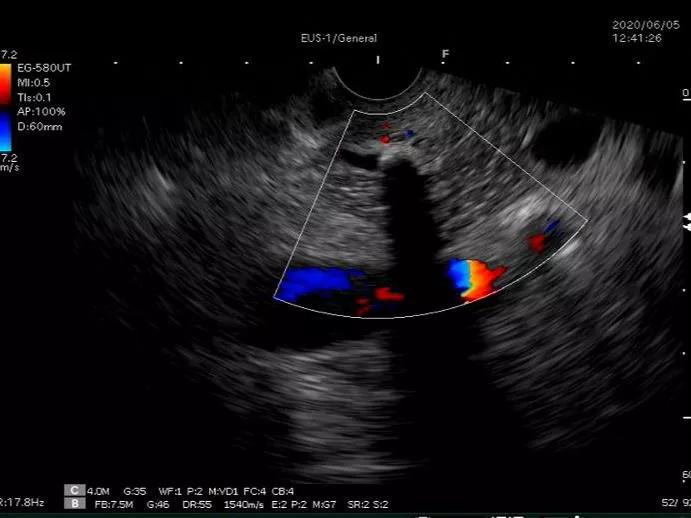

林涛主任决定行超声胃镜检查,但超声内镜对于胆胰病灶的检查操作难度比较大,胆管的直径很细,超声内镜检查的难度更大。经过林涛主任及内镜中心团队的密切配合,在胆总管末端即壶腹部发现了高回声的占位病灶,其后可以看到明显的声影。确认为胆总管末端结石。